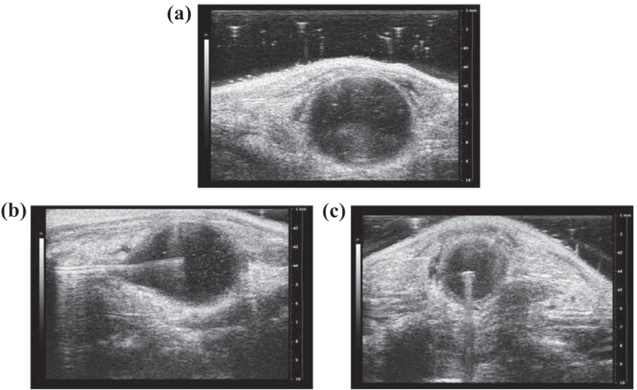

Fibre insertion and positioning was determined via ultrasound (VEVO 2100) as shown in figure 2. The fibre was threaded through a catheter attached to an adapter with a resealable end to push the fibre through and a second end with a syringe to fill the bladder with air. An in vivo NIR tolerance test at energy densities of 50 and 100 J cm−2 and time of 30 s with a 360° radiating fibre was conducted. Mice were euthanized 24 h after treatment, and H&E staining on bladders was used to determine if damage was caused to the urothelium.

Figure 2. Ultrasound images of fibre positioning in bladder. Ultrasound images of before (a) and after diffusing fibre centreed in C57BL-6 mouse bladder in the x–z (b) and x–y (c) plane. A centred diffusing fibre ensures one session is required to treat the entire bladder and isolated residual tumour cells.